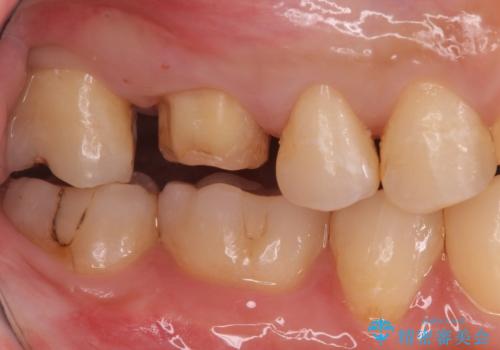

不適な樹脂の詰め物 被せ物で被覆

- 奥歯の劣化・変色した樹脂の詰め物をやり直していきます。

セラミックのインレーでは強度に不安が残るため、セラミッククラウンで全体を被覆することとしました。